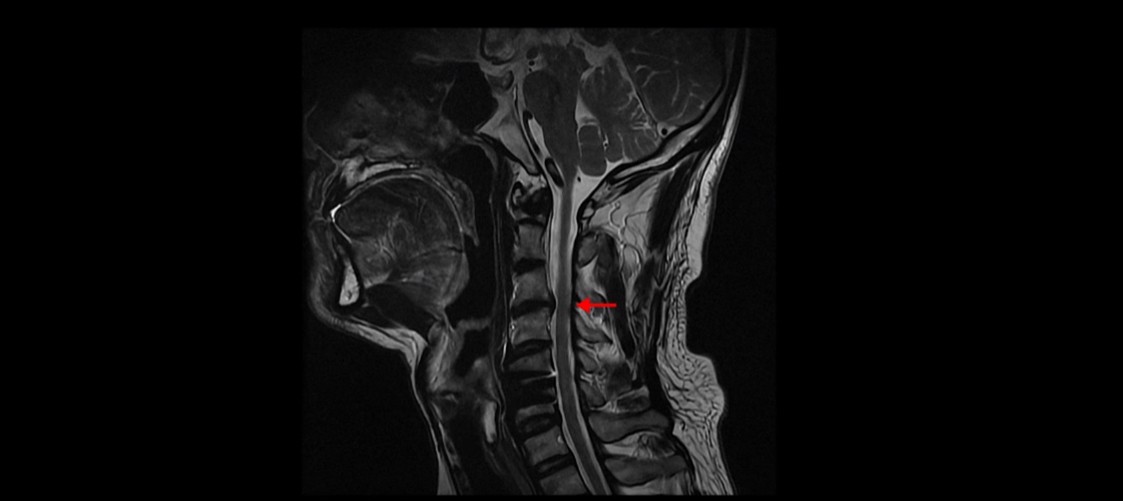

이 환자분의 증상인 목, 어깨, 등 통증, 두통, 어지럼증, 눈 불편함, 시력 저하 이런 증상들은 원래가 목 근육 문제와 매우 밀접하게 관련된 증상들입니다. 저희가 목디스크, 목협착 환자의 99%는 거북목 환자라고 말씀드렸습니다. 이런 증상들은 거북목과 매우 밀접한 관련이 있습니다.

이런 목의 형태를 가지고 있으면 만성적으로 목과 어깨가 아플 가능성이 높습니다. 앞으로 밀려나간 머리를 목 근육이 붙잡고 있어야 하기 때문에 목, 어깨 근육이 뭉치면서 아프기 쉽습니다. 또 목 근육과 머리 뒤쪽 근육이 연결되어 있으므로 목 근육이 뭉치면 머리 근육도 뭉치면서 두통도 생길 수 있습니다. 또한 거북목은 목 앞쪽 근육이 짧아지면서 심하게 뭉치는데, 이 목 앞쪽 근육 사이로 얼굴 쪽으로 가는 수많은 신경과 혈관이 지나갑니다. 그래서 신경과 혈관이 영향을 많이 받기 때문에 어지럼증, 눈 통증, 눈 침침함, 이명 같은 증상이 생길 수도 있습니다.

목디스크의 제일 중요한 증상은 한쪽 손과 팔, 어깨 특히 견갑골 쪽 통증과 저림 증상입니다. 앞서 말씀 드린 그 외의 여러 증상들은 목 근육 문제와 매우 밀접한 관련이 있습니다. 그래서 목디스크 수술 후 한쪽 손, 팔, 어깨 저림 증상이 없어졌다고 해도 이런 다른 여러 복합 증상들은 좋아지지 않을 수도 있고 또 목 근육 문제로 인한 이런 여러 증상들을 목디스크 증상으로 오진했을 수도 있습니다.